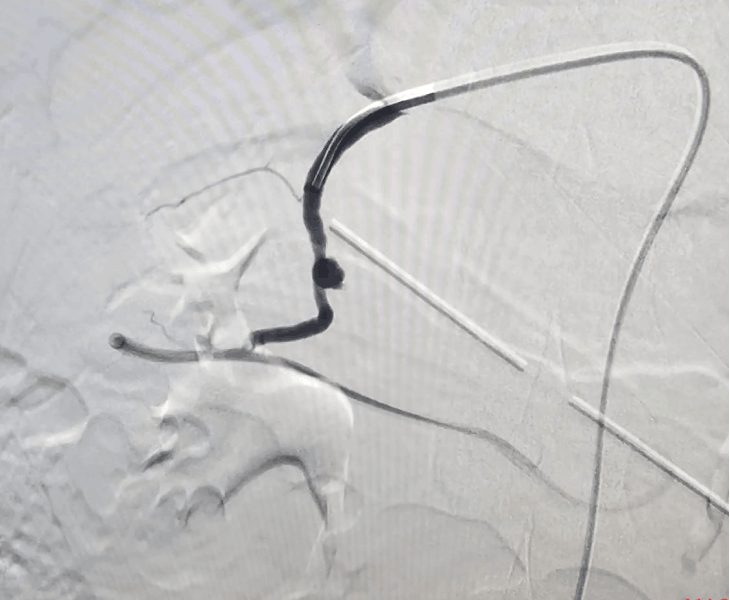

Embolization is performed in a catheterisation lab under fluoroscopy (X‑ray) guidance, usually through a tiny puncture in the groin or wrist artery.

- Catheter angiography: contrast is injected to locate the pseudoaneurysm and bleeding source.

- Super‑selective catheterisation: a microcatheter is advanced into the specific branch feeding the pseudoaneurysm.

- Embolization: coils and/or other embolic agents are deployed to stop blood flow to the pseudoaneurysm.

- Post‑embolization check: repeat angiography confirms complete sealing with preserved flow to normal tissues.